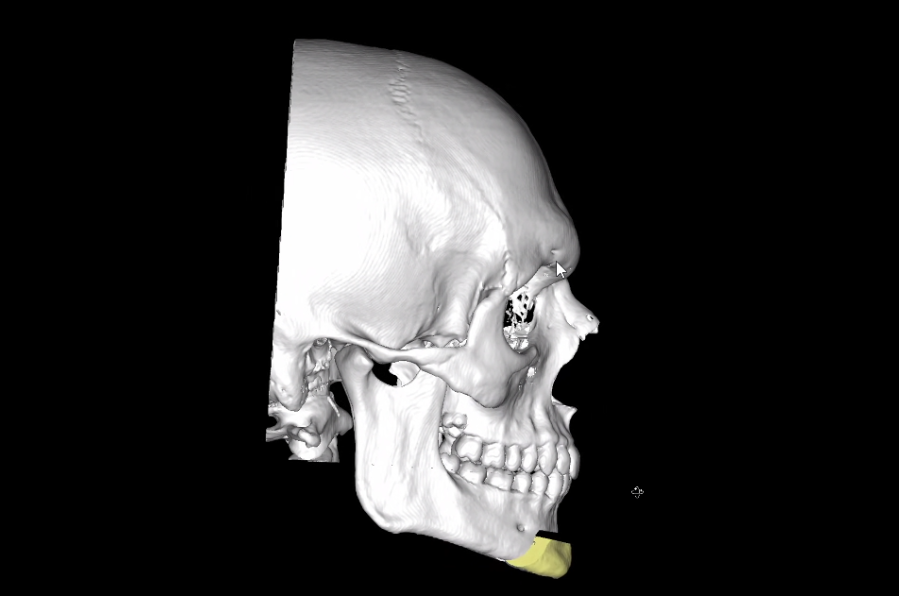

Here are the predicted CT Scans with the Genioplasty:

Here are the predicted CT Scans with the Genioplasty: